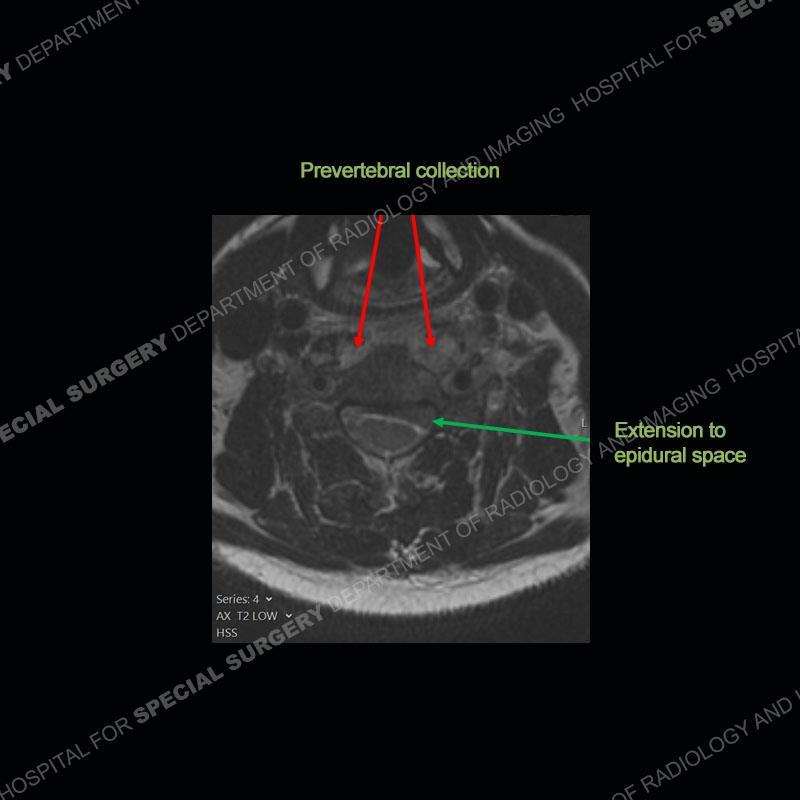

The radiographs demonstrate a prevertebral soft tissue fullness centered at C5-C6 that persists even on extension. There is a slight loss of disc height at C5-C6. The CT more readily shows the prevertebral soft tissue swelling at C5C6 where there is a punctate focus of gas. On the MRI, there is a marked amount of edema and a heterogeneous collection in the prevertebral soft tissue at C5-C6. Edema is present of the C5 and C6 vertebral bodies with a loss of the normal architecture about the disc space. A heterogeneous epidural collection has formed that causes compression of the spinal cord asymmetric to the left side and also precipitates severe left sided neural foraminal stenosis.

Diagnosis: Spontaneous Retropharyngeal Abscess (RPA) with Discitis/Osteomyelitis, Epidural Abscess, and Cord Compression

Spontaneous RPA in the non-immunocompromised, adult population is an extremely rare occurrence. RPA most frequently occurs in young children and most typically after a URI. It may be associated with torticollis in Grisel syndrome. In the adult population, the pathomechanism is not well understood with some suggesting a hematogenous spread or perhaps a seeding from the adjacent aerodigestive tract. The abscess as in this case can extend to involve the vertebral column and then the neural elements. At times, this process can be treated with antibiotic therapy alone but when there are neurologic symptoms and especially progression of neurologic symptoms, surgical intervention is warranted. In this case, given the extent of the process and the patient’s clinical situation, a corpectomy with fusion was performed in addition to antibiotics.